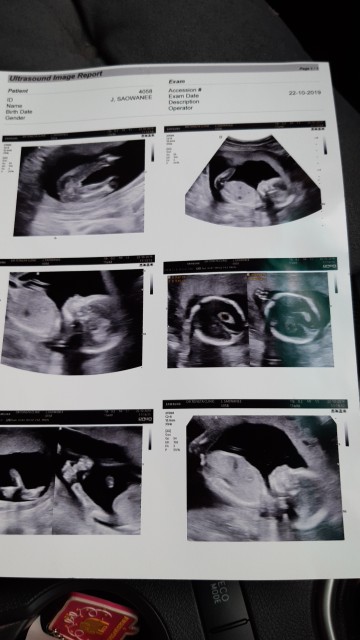

4เดือนครึ่งค่ะ ผชค่ะ

5เดือนชัดพอมั้ยค้ะ555